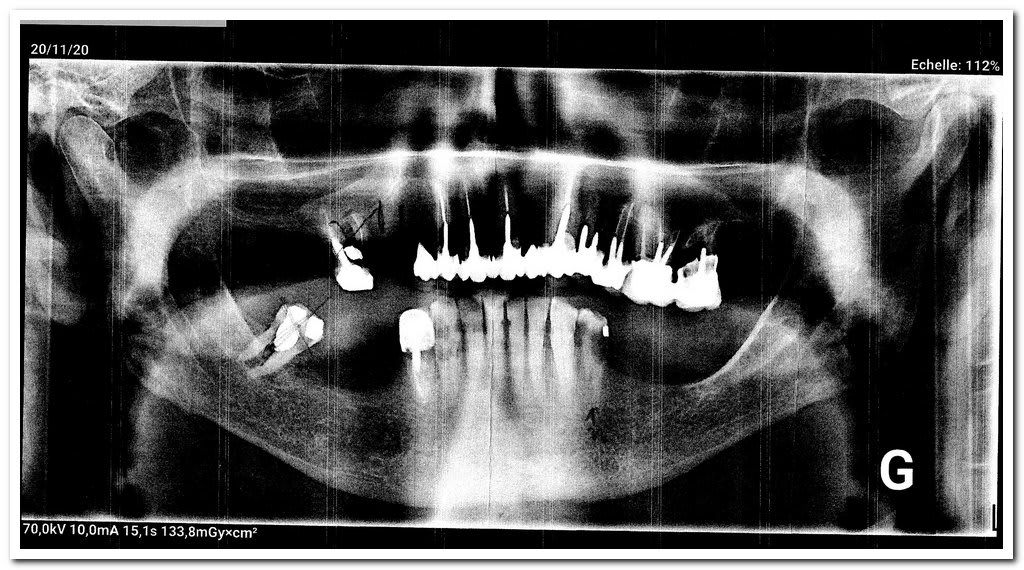

la radio panoramique est a étudier.

attend je te fais passer la radio ... meme les cotation des extractions ne sont pas comme chez nous ! ...

47 ... racine incluse ?

Et la bouche actuelle du patient est dégueu : 16 pas extraite, provisoire 32 tombée, les dents manquantes non remplacées sur le stelite mandibulaire. Rien n'est proposé pour la 27.